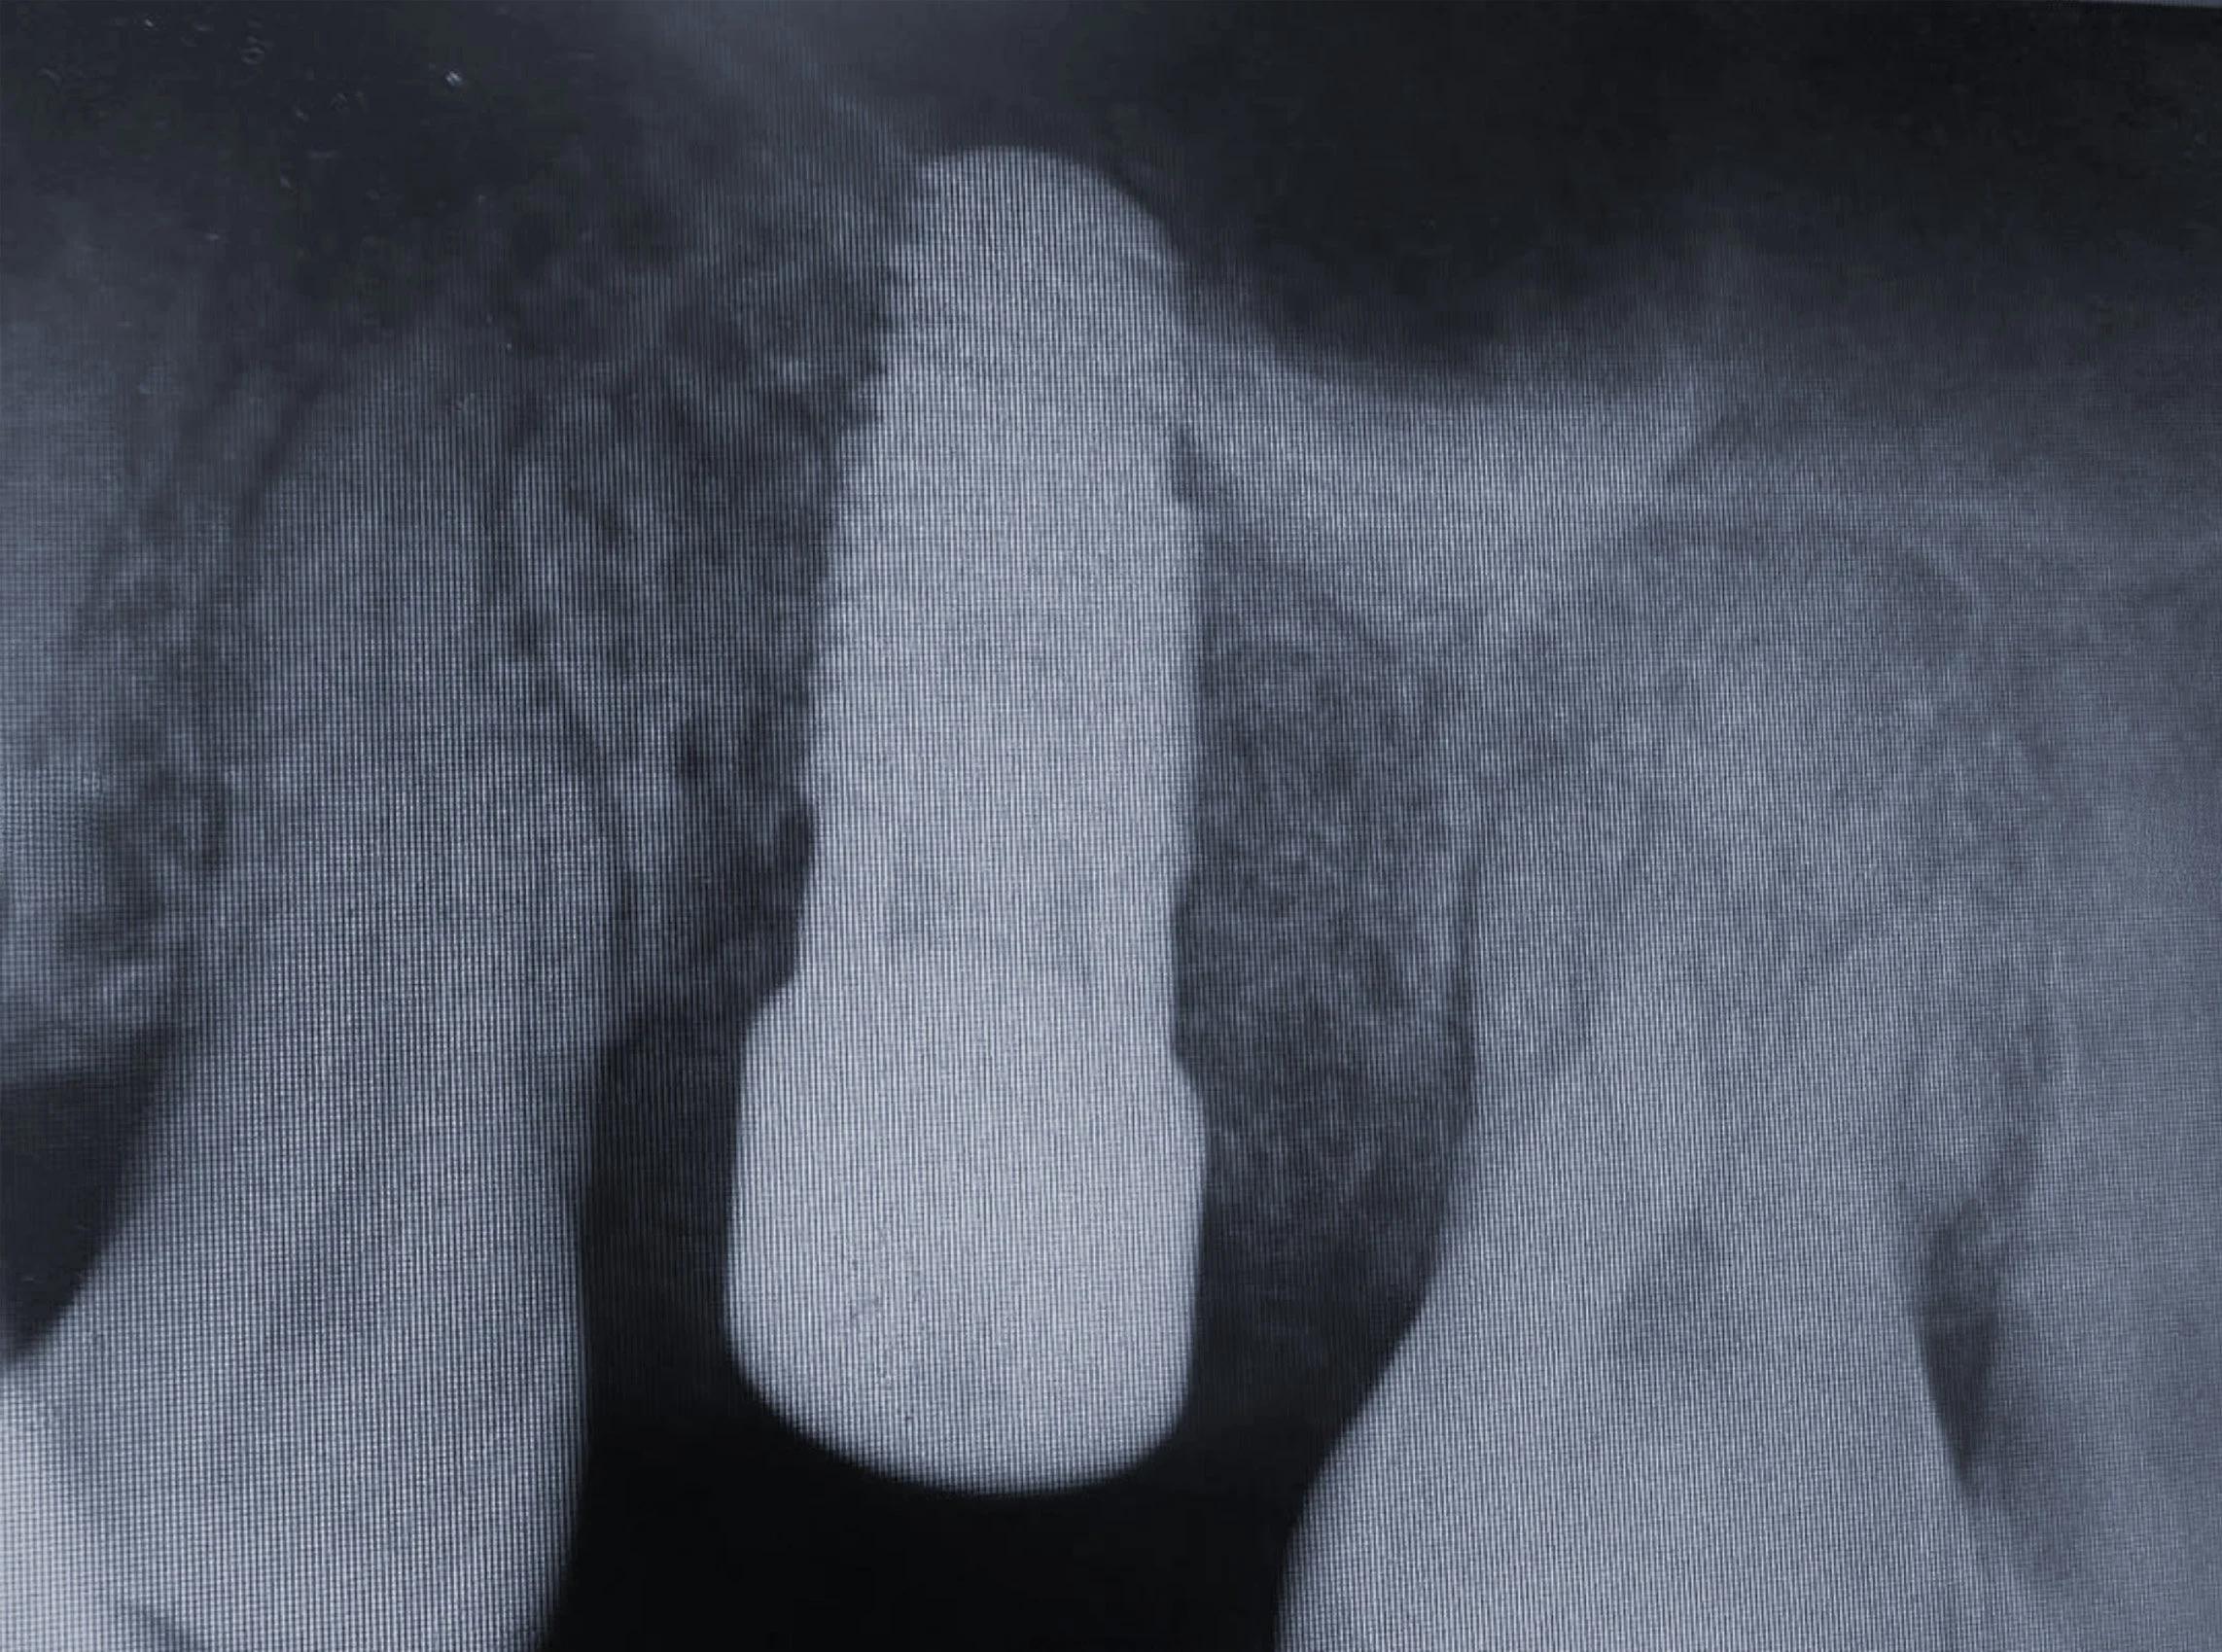

Step 3 — Implant Placement & Occlusal Sinus Lift

During implant placement, a sinus lift was performed to increase vertical bone height and ensure long-term stability. The implant achieved excellent primary stability and integration.